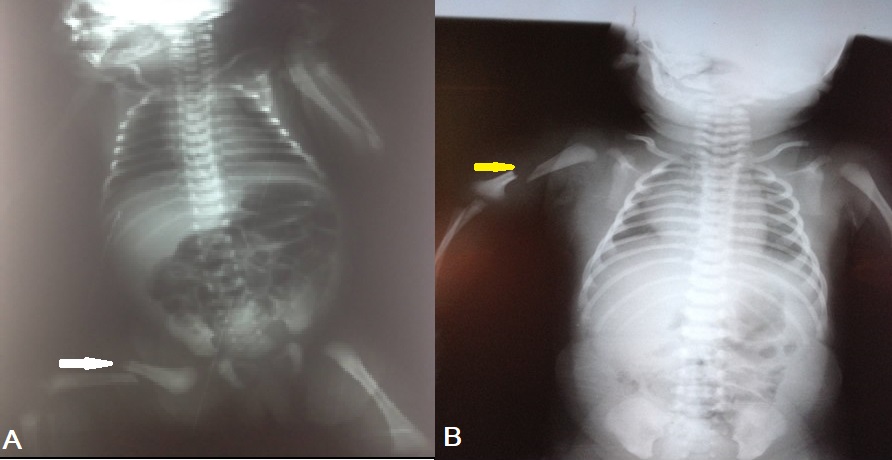

Skeleton trauma: A male term newborn weighing 3.8kg born by C-section due to failure of progression of the delivery. There were no reported difficulties in delivering the baby who cried immediately at birth with an Apgar score of 9. A few hours later, the baby developed irritability and inconsolable cry along with swelling of the right lower limb. Radiographic examination revealed a diaphyseal fracture of the right femur (Fig. 2A) . Immobilization of the limb with a bandage for 3 weeks was done and the baby discharged home. The follow-up showed a good outcome.

Another male newborn with the gestational age of 40 weeks, cephalic presentation, weighing 4 kg, was born by spontaneous vaginal delivery. This fetal macrosomia was complicated with brachial plexus injury, probably due to traction of the neck at birth. Radiographs of the shoulder and upper arm showed a fracture of the right humerus(Fig. 2B). Both lesions were managed in our department immediately by immobilization by calf strip for 4 weeks, and the limb was held to the body by a scarf. One month later, rehabilitation was started. A good functional outcome was obtained after 6 months.

A) Femur fracture (white arrow) in the first case with skeleton injury. B) Humerus fracture (yellow arrow) in the second case of skeleton injury.